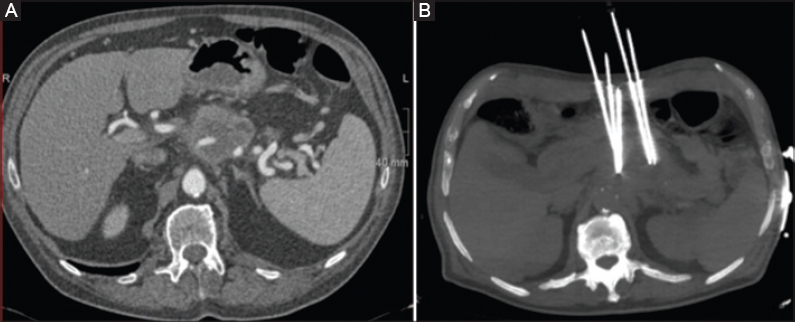

Radiofrequency Ablation Of The Pancreas Ii Intra Operative Ablation Of Non Resectable Pancreatic Cancer A Description Of Technique And Initial Outcome Insight Medical Publishing

View Of Percutaneous Ablation Therapies Of Inoperable Pancreatic Cancer A Systematic Review Annals Of Gastroenterology